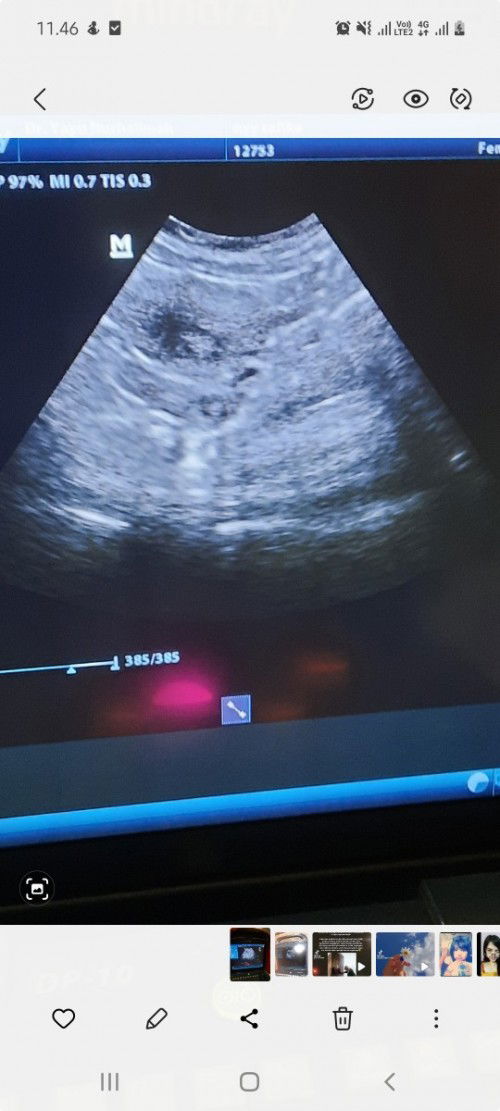

Bunda disini ada yg pendarahan saat hamil muda lebih dari 2 minggu tapi janin nya sehat ? Sharing dong bun, biasanya kenapa ya bisa pendarahan gitu ?? Soalnya aku pendarahan nya lumayan banyak sehari bisa ganti 2x panty liner, tapi kadang sehari gaada besoknya ada pagi2 aja. fyi : aku udah ke dokter dikasih penguat, hari senin besok disuruh kesana lagi.. mohon doa nya semoga sehat janin nya 🤲#bantusharing #ingintahu #pleasehelp